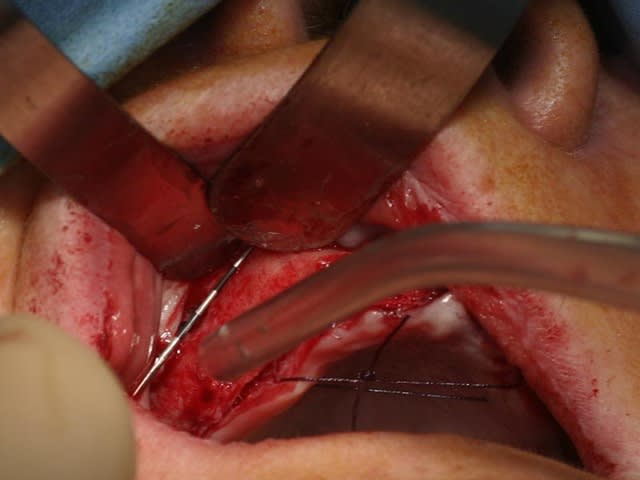

bon, toujours aussi speed je suis, mais après certaines réclamations, et malgrès ma réticence à poser un cas non "consolidé", voici en avant première mon premier all on 4, version photos ratées et non retouchées, mais... speed je suis je vous disais ;)

sto le bla bla, et pasons le diaporama... bon voyage au pays de la mise en charge immédiate totale au maxillaire de fille carole sur dame ginette, une patiente en or que j' adore, et pour qui je suis très très heureuse d' avoir pu réaliser cette chirurgie et la première étape prothétique.....